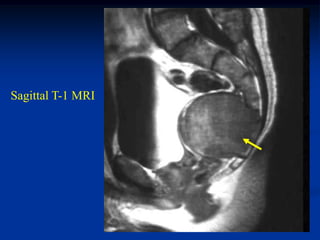

Case #1104.1                Chordoma L-1

49 year male with back

pain for 6 mos and recent

paraparesis

Sag T-1   T-2